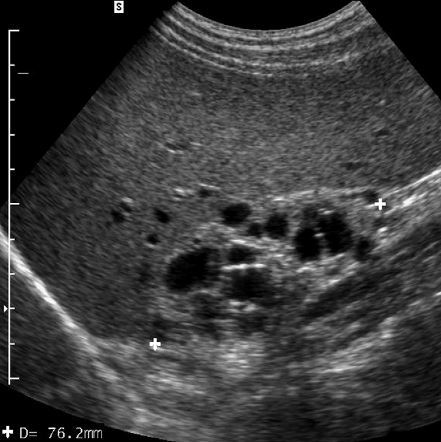

Caroli’s disease

• central dot sign = cystic lesions with central solid components containing blood flow

• complications

• biliary stones

• bild duct obstruction

• cholangitis

• liver abscess

• hepatic fibrosis –> portal hypertension

• cholangiocarcinoma

• the kidneys may also be affected with a variety of cystic diseases